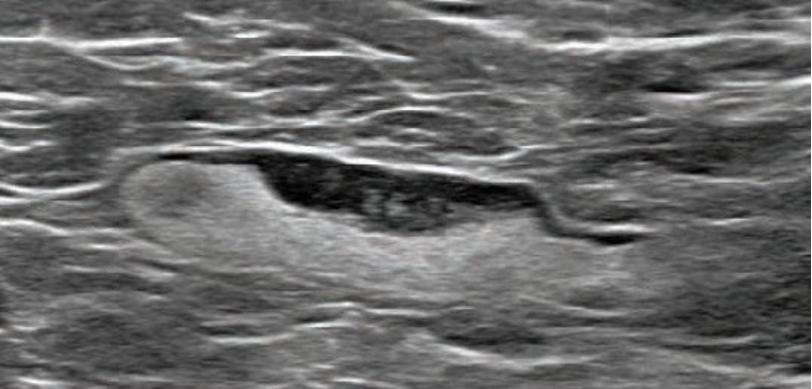

Details